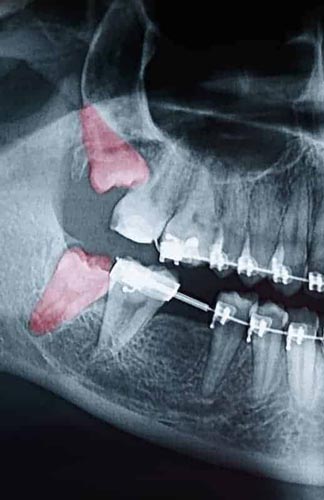

Though some patients may not require the removal of their wisdom teeth, most often, it’s needed to protect your overall oral health. Wisdom teeth can begin to grow in sideways, only partially erupt, or even get stuck beneath the gum and bone. Known as impacted teeth, those that get stuck may resort to shifting position as the try to find a pathway for eruption. When wisdom teeth don’t erupt through the gumline properly, they can create severe problems for the patient, including:

In order to evaluate the state of your wisdom teeth, we’ll first do a thorough examination and take x-rays of your mouth. This will help us determine if your wisdom teeth pose a current or future threat to your oral health. Early detection of issues results in better outcomes for our patients, so we recommend the first evaluation be completed in a patient’s mid-teenage years.